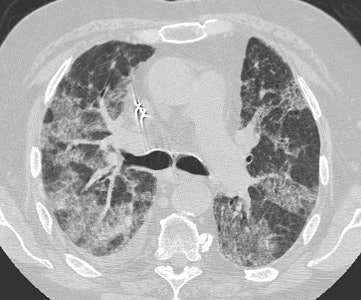

Diffuse Alveolar Damage: The patient below was admitted to the intensive care unit with increasing dyspnea. HRCT imaging revealed patchy areas of ground glass opacity and consolidation within the lungs bilaterally. There were prominent underlying reticulations within the areas of airspace disease. An open lung biopsy was performed and demonstrated diffuse alveolar damage. The etiology was not clinically apparent.  |

![]() ![]()  |